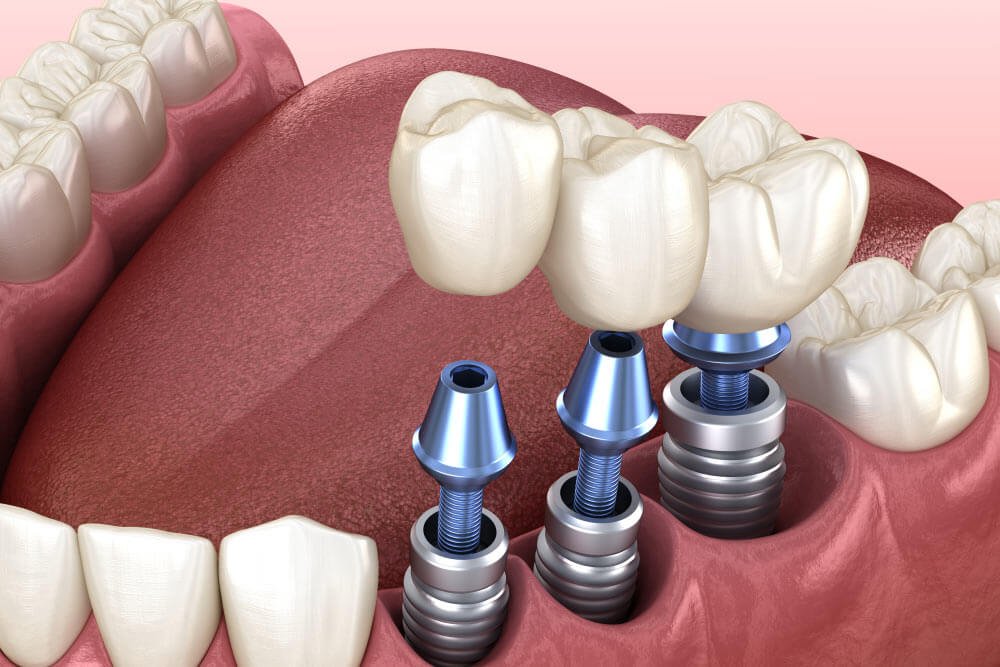

The Dental Implant Process

Step 1: Consultation & Evaluation

Step 2: Implant Placement

Step 3: Healing Period

Step 4: Crown Placement

The result is a strong, stable, and natural-looking replacement.

What Are Dental Implants?

Dental implants are permanent replacements for missing teeth. They consist of a titanium post placed into the jawbone, which acts as an artificial tooth root. A crown is then attached to restore the appearance and function of a natural tooth.

Dental implants look, feel, and function like real teeth.